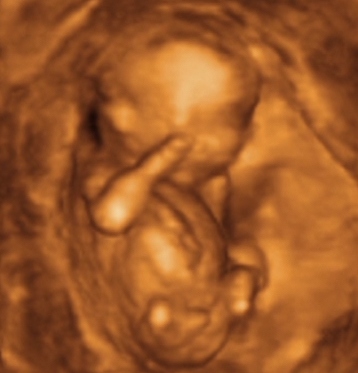

Mi megjöttünk az uh-ról! :D Uram sajna nem ért oda :(, de mi mamával áhitattal néztük Manó Gyereket fél órán keresztül! :D

Hála az égnek, minden rendben van, mindene megvan és működik is, minden tökéletes méretű rajta! Kóros elváltozás sehol nem látható! (A dvd-t most fogjuk megnézni büszke apájával... :wink: )

...Uram gazdagabb lett 10 Ft-tal... :oops: :cry: :twisted: :P

KISFIÚ!!! Ennyit a megérzésemről... :? :cry: :wink: :lol: Üdv a pocakomban Dániel Áron! :D